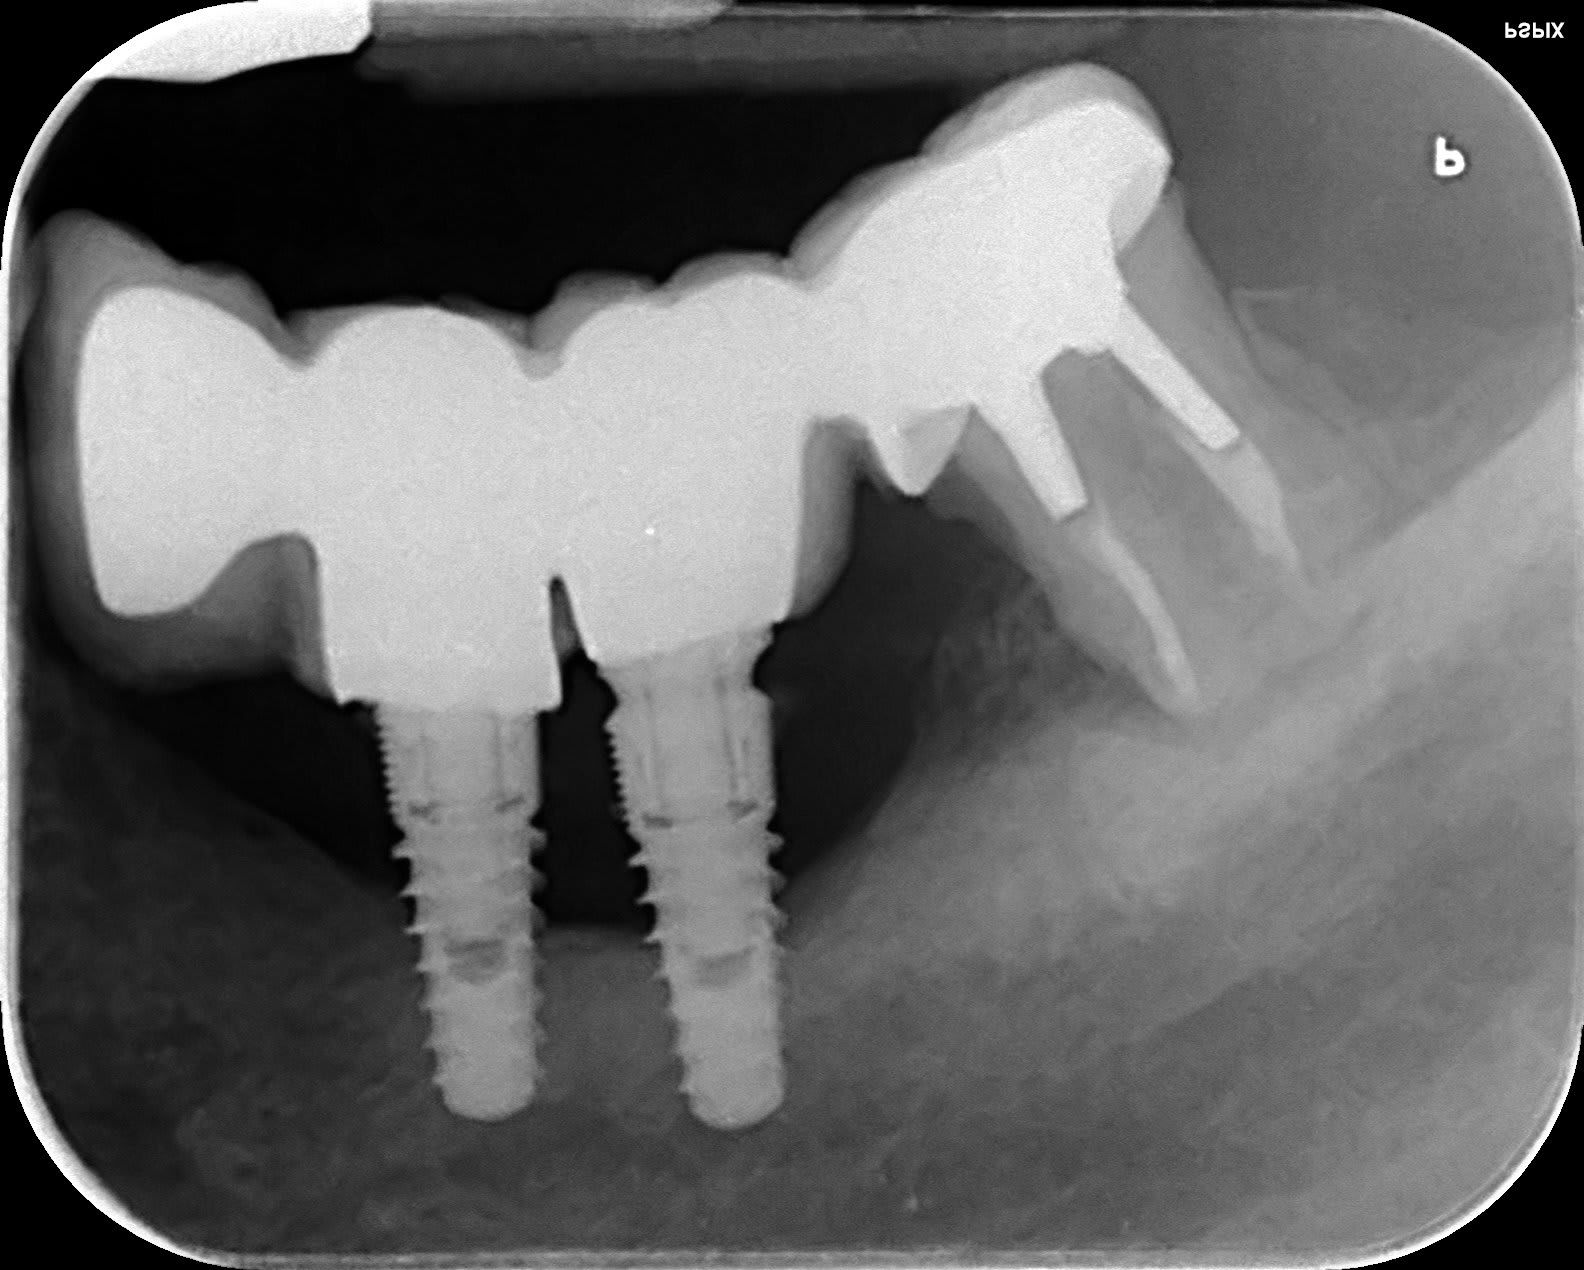

Hum!...

Péri imp kvhkde - Eugenol